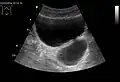

• Calyceal diverticula are usually asymptomatic, but if a stone becomes lodged in the outpouching, they may present with pain.[14]